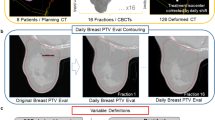

Figure 2 shows the image registration of the verification CT (orange) with the planning CT (blue). Figure 2a (Patient #4) had a counter-clock wise roll posture error so that the alignment on bony structures required a clock-wise roll correction, as illustrated in VPlan-B. Due to the counter-clockwise roll posture error, gravity created a breast tissue roll counter-clockwise, to a degree larger than the posture error alone. Therefore, a more clockwise roll correction was required when aligning with the breast tissue, as shown in VPlan-T. The alignment on skin (VPlan-S) showed an overall similar alignment as VPlan-T, but with slightly better alignment on the CTVbreast near the skin and slightly worse alignment on the CTVbreast near the chest wall. Figure 2b (Patient #11) had a good posture setup. However, due to the large (1361.7cm3) and pendulous breast, the breast shape changed, requiring a counter clockwise roll to align the breast tissue (VPlan-T) and the skin (VPlan-S). The image registration for the patient who developed edema during treatment is shown in Fig. 2c (Patient #7); an increased WET along the beam path was observed.

Example of image registration between the verification scan (orange) and the original planning scan (blue) for (a) Patient #4, who had a large posture error and breast error, (b) Patient #11, who had good posture setup but a large breast error, and (c) Patient #7, who developed breast edema during the treatment. The blue or orange color only appears in regions of misalignment. The solid yellow contour represents the CTVbreast contour on the original scan and the dashed yellow contour represents the CTVbreast on the verification scan